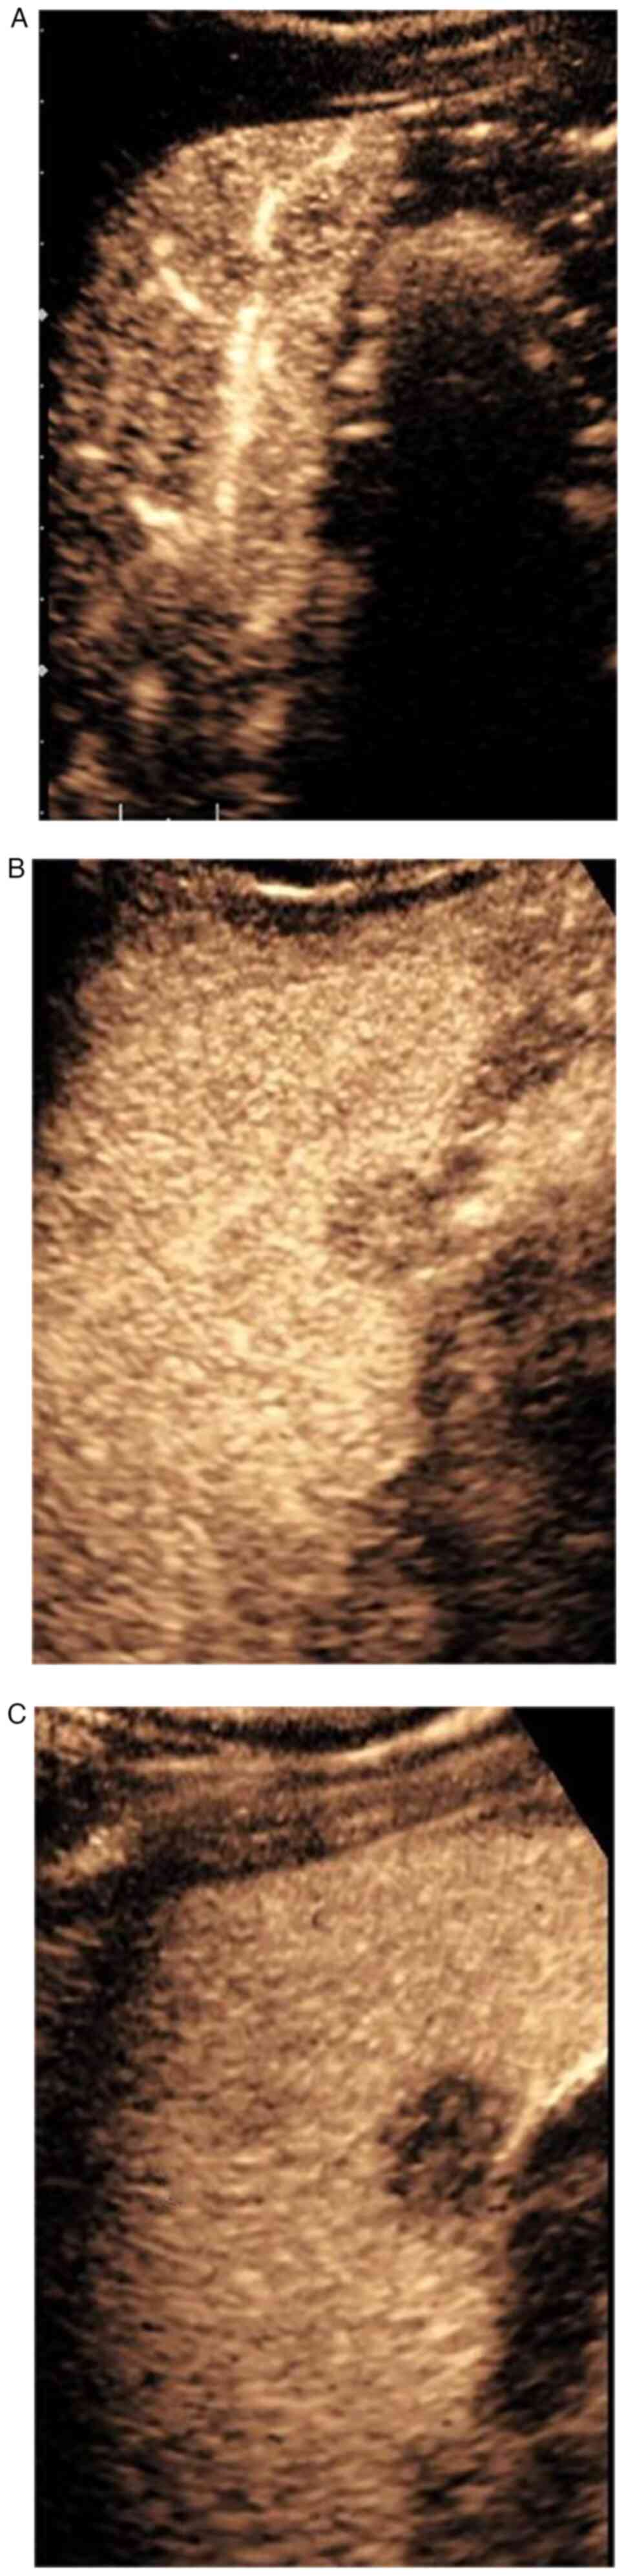

Characteristic contrast‑enhanced ultrasound findings of hepatic epithelioid haemangioendothelioma: A case report and literature review

Hepatic epithelioid hemangioendothelioma (HEHE) is a rare liver tumor, which is usually diagnosed by pathological examination, since the diagnostic imaging criteria remain to be defined. However, contrast‑enhanced ultrasound (CEUS) may reveal the characteristic features of HEHE to aid diagnosis. In the present study, two‑dimensional ultrasound examination of a 38‑year‑old male patient showed a mass in the right liver. CEUS showed an S5 segment hypoechoic nodule, and imaging features resulted in the diagnosis of HEHE. Surgery was shown to be an appropriate and successful treatment for HEHE. In conclusion, CEUS may be valuable for the diagnosis of HEHE, thereby avoiding the serious consequences of misdiagnosis.

Figure 1

Figure 2

Figure 3